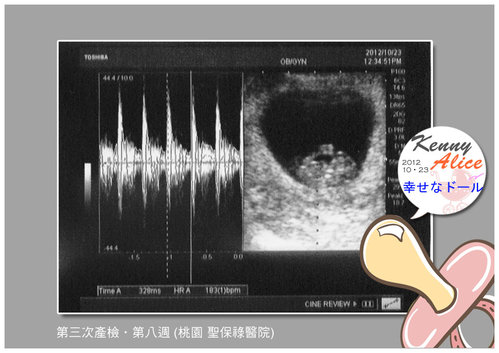

===== 小B寶的心跳聲 蹦 蹦 蹦 楊醫生說 很好 很強 很有力唷!! =====

一聽到小B寶的心跳聲....我的眼淚不自覺的落了下來~說不出的感覺....太感動了!!